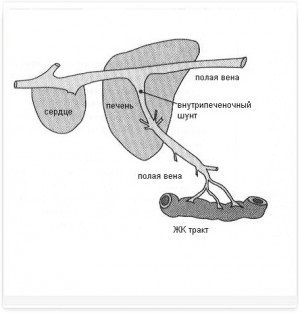

Porto (portocav) șunturi - este conexiuni vasculare anormale între vena portal hepatic (vas de sânge care se conectează tractul gastrointestinal la nivelul ficatului) și circulația sistemică (Figura 2, 2a).

Schema Fig.1 a fluxului sanguin normal de portal

Figura 2 și 2a. Schemele fluxului sanguin portal patologic